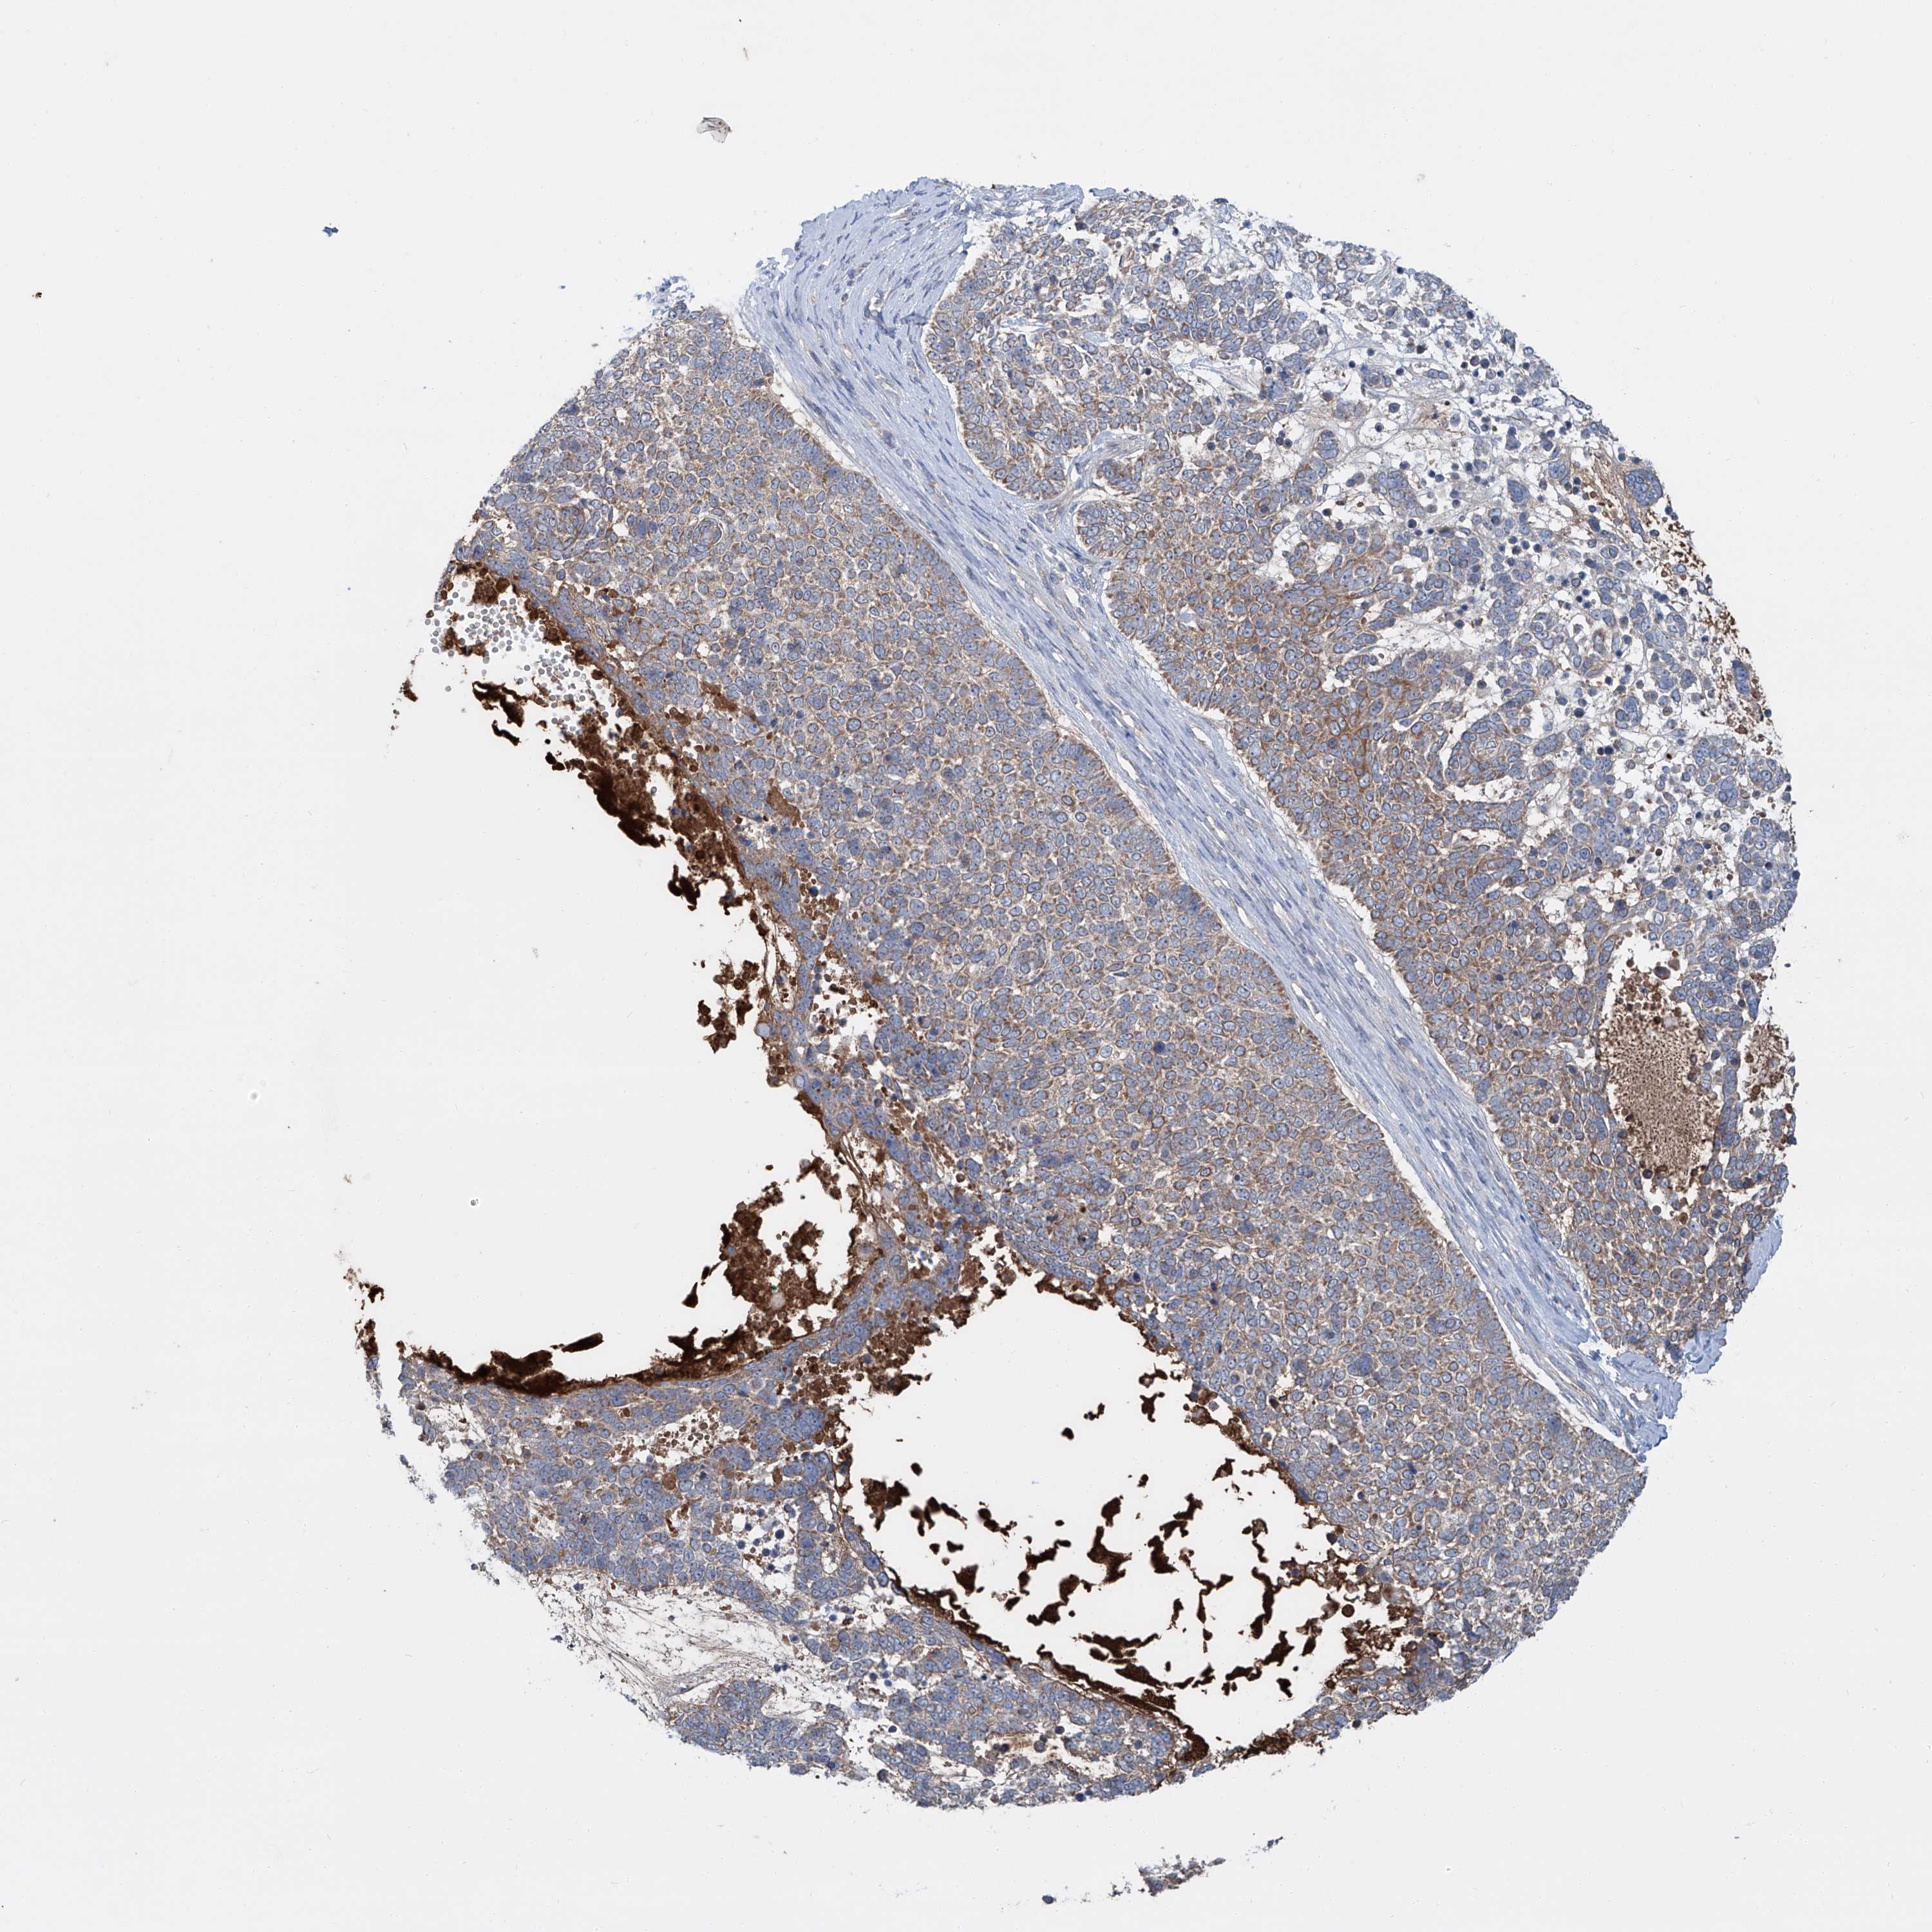

Basal cell and squamous cell cancer

SKIN CANCER - Protein expressioni

A mouse-over function shows sample information and annotation data. Click on an image to view it in a full screen mode. Samples can be filtered based on level of antibody staining by selecting one or several of the following categories: high, medium, low and not detected. The assay and annotation is described here.

Antibody stainingi

Antibody staining in the annotated cell types in the current human tissue is reported as not detected, low, medium, or high, based on conventional immunohistochemistry profiling in selected tissues. This score is based on the combination of the staining intensity and fraction of stained cells.

Each image is clickable and will lead to virtual microscopy that enables deeper exploration of all samples and also displays staining intensity scores, fraction scores and subcellular localization as well as patient and tissue information for each sample.

Antibody HPA031794

Staining

Low

Intensity

Weak

Quantity

<25%

Location

Cytoplasmic/membranous,nuclear

Squamous cell carcinoma, metastatic, NOS